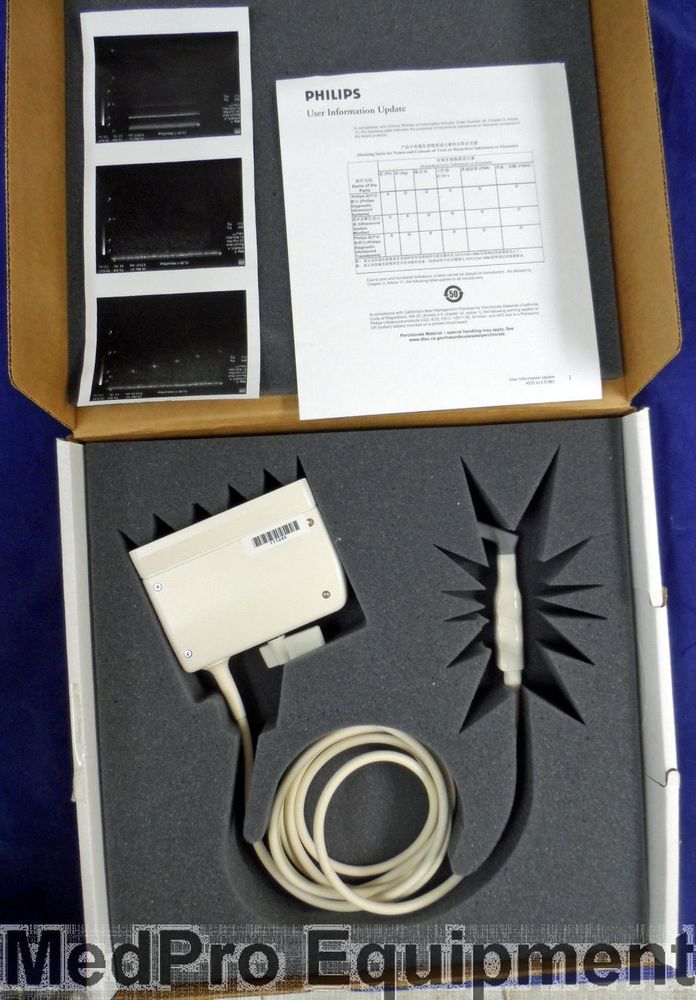

Philips X7-2 Ultrasound Probe Transducer

Sale price$ 1,392.60